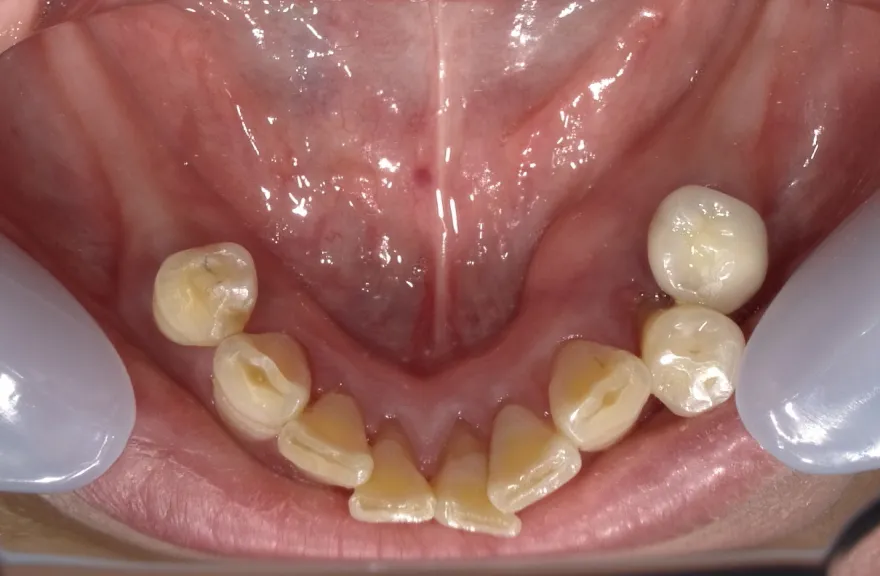

【治療例 5】上の歯がグラグラで困っている 62歳

- 相談内容

- 数年前に全体的に治療したが、上のつながっている歯がグラグラして噛めないということで来院されました。

- 治療費用・方針

-

上顎は5本の歯を保険のブリッジ治療で連結してある状態でした。どの歯の状態も良くなく、今回なんとか治療を行ったとしても近いうちに再びトラブルを起こしてくることが予想されました。

下顎は9本の歯が残っており、虫歯はあるものの差し歯として使える状況でした。

しかし、患者さんとの話し合いの中で、「数年前に行った治療なのに再び全てやりかえないといけないのは単純にしんどい。もうやりかえのないようにしたい」という患者さんの強い思いが伝わってきました。

今回で完全に治療をやり切ってしまい、今後は最小限の介入で歯科と付き合えるよう、上下顎残っている歯の全ての抜歯、必要な本数のインプラント埋入、上顎は総義歯形態で対応することとしました。 - 治療のリスク